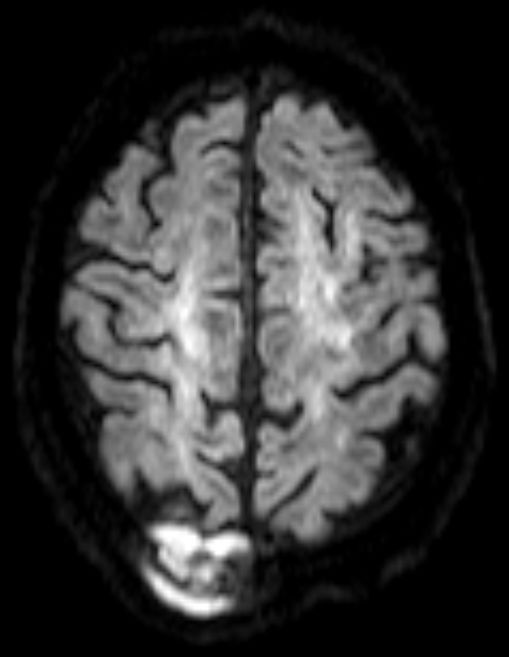

Im DWI-MRT macht das Lymphom ein besonders starkes Echo.![]() | |||